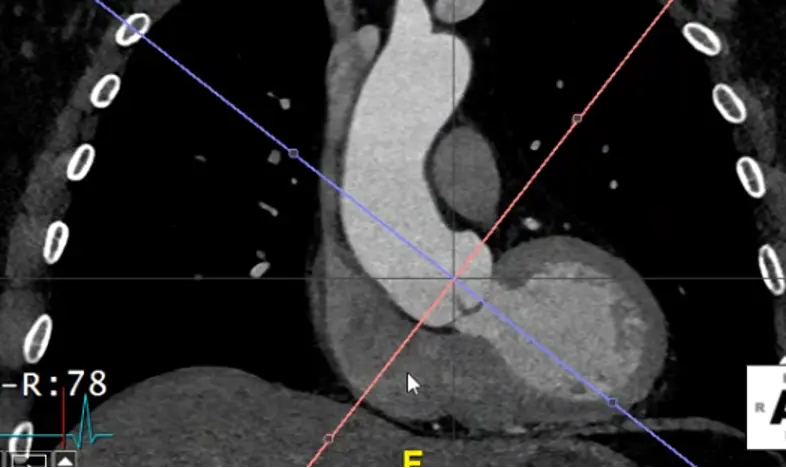

- Hit

Xto grab your cross-hairs. You will drag the cross hairs to the middle of the sinuses of Valsalva in the axial view window. - In your coronal view window, there is a pink/red line with a small circle. Drag this circle to line up the pink/red line to be perpendicular to the wall of the sinus of Valsalva. The blue/purple line should be in the center of the long-axis of the aorta at the sinus of Valsalva.

- Similarly for your sagittal view, you will want your pink/red line to be perpendicular to the sinuses of Valsalva. You will also want your green line to be in the center of the long-axis of the aorta at the sinus of Valsalva.

- Once youâve lined things up, in your axial view window you will now have what is called a âtrue short axisâ of the aorta at that level.